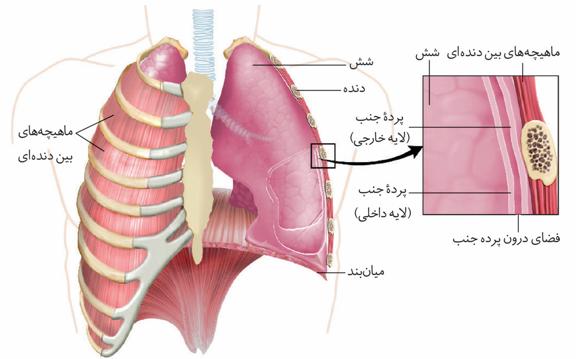

ششها را نیز پردهای دو لایه از جنس بافت پیوندی در بر گرفته است.